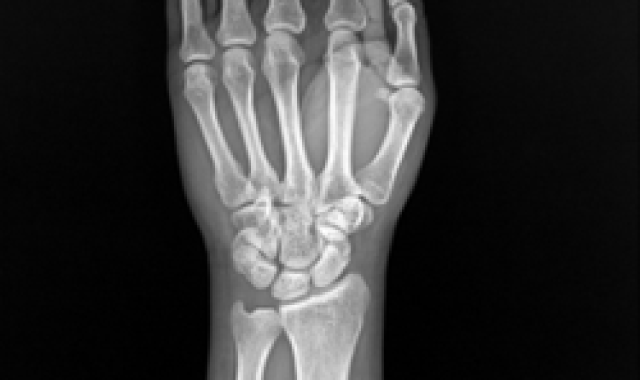

주상월상인대파열 진단법

X-ray 진단으로 보이지 않을 경우

→ 초음파, MRI 영상 검사

주상골, 월상골 사이 인대는 아주 작아 MRI 로 진단이 어려운 경우

→ 손목관절 내시경을 통해 진단

힘주지 않았을 때 우측

힘주지 않았을 때 좌측